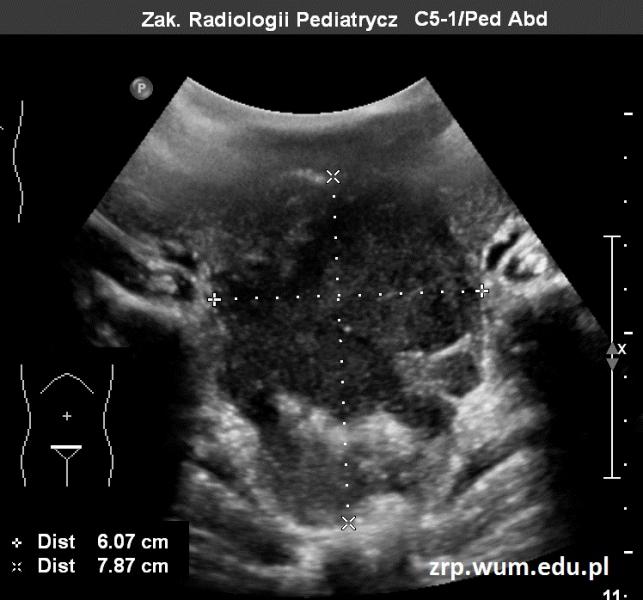

Przypadek 38: 4-letni chłopiec został przyjęty do Szpitala z powodu podejrzenia rozsianego procesu nowotworowego. W wywiadzie od 2-3 miesięcy narastające osłabienie i apatia dziecka, brak apetytu, narastanie obwodu brzucha. Od ok. miesiąca narastająca bladość.

Rozpoznanie: W badaniu USG uwidoczniono w jamie brzusznej rozległe masy guzowate (pomiary między kursorami). Skierowany do dalszej diagnostyki.